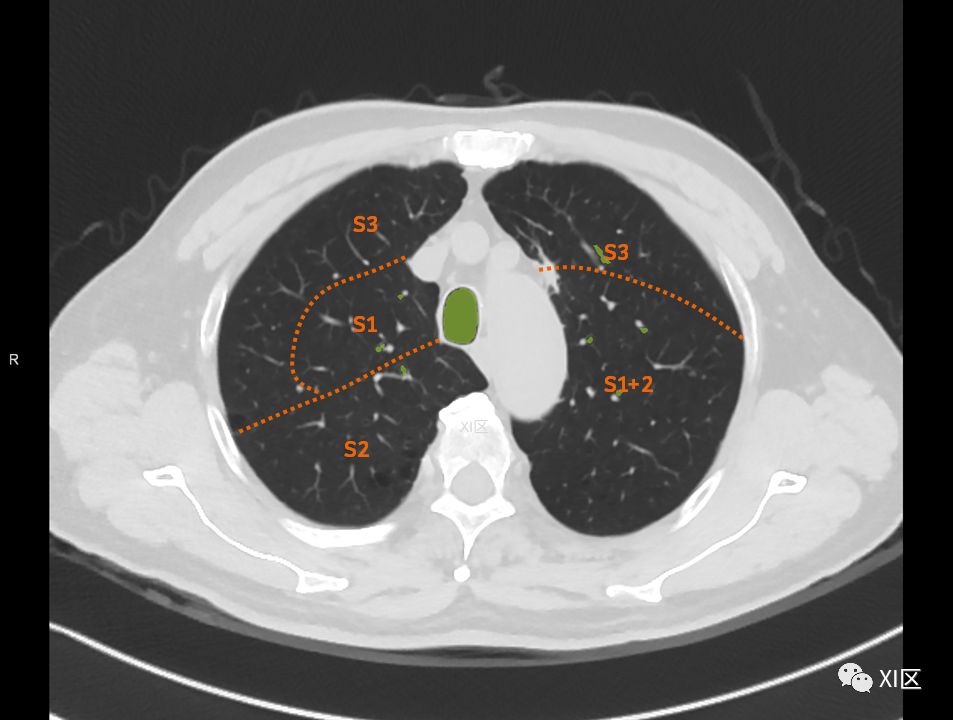

肺的分段

肺的断层分段示意图

在进行肺的分段时,可以上下观察浏览,沿着相应气管的走形可以更容易准确地进行分段。